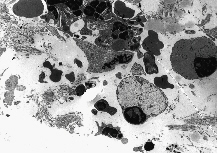

Fig. 8B: This figure refers to an experiment with i.v. injection of 3-THPP at D T1 = 6 days and D T2 = 18 hrs. The capillary shown here lacks totally a normal endothelial lining. All the crowded erythrocytes seem to be held together by an abrupt "lining" of collagen fibres. Some erythrocytes appear nevertheless to have leaked into the structure-less perivascular tissue, which here contains some cell debris. Fibrin-containing structures are seen among the erythrocytes.

Fig. 8D: This figure is taken from an experiment with i.v. injection of 3-THPP at D T1 = 6 days and D T2 = 18 hrs. A macrophage is shown with its nucleus in a marked peripheral position and its cytoplasm filled up with unidentified material. Part of another cell, seen up to the left, appears to contain the same intracellular substances. Part of a third cell's cytoplasm, seen down to the left, contains empty vacuoles.

Fig. 8E: This figure refers to an experiment with i.v. injection of 3-THPP at D T1 = 6 days and D T2 = 18 hrs. Lymphocytes are also seen to be influenced by photochemotherapy. Two lymphocytes are located in the right part of the figure, both with pycnotic nuclei strained to the cell membrane. The cytoplasm seems swollen and filled up with structureless material of variable darkness, concealing all traces of normal organelles. Fragments of leucocyte material and collagen debris surround the lymphocytes.

Fig. 8F: This figure corresponds to Video sequence 5, with D T2 = 2 hrs. A great number of the granulocytes in tissue treated with porphyrins and light appear to be highly activated, with swollen knob-like cytoplasmatic extrutions.